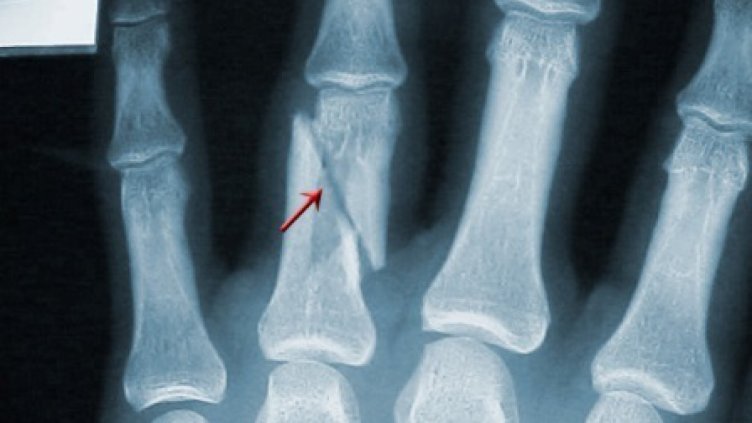

Рецидивист от Синдел преби и счупи пръстите на мъж в центъра на Варна. Екшънът се разразил след скандал между двамата.

52-годишният пострадал е с два счупени пръста на ръката.